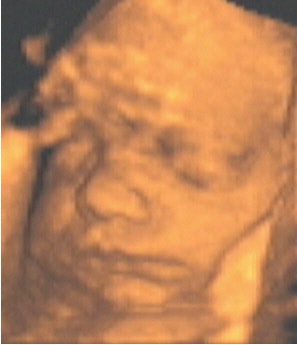

![]() |

| Figure 6, an example of a televised snapshot of the fetus at 34 weeks gestation. Image courtesy of Dr. Stefano Ciatti. |